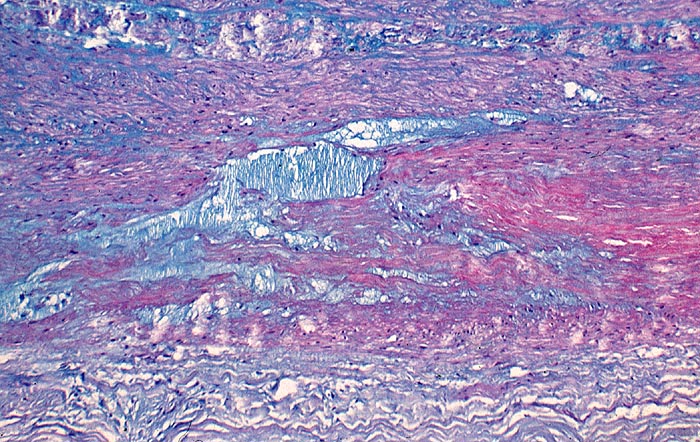

PathoPic – image database / PathoPic ID 2851 - Zystische Mediadegeneration Erdheim Gsell

Zystische Mediadegeneration Erdheim Gsell

Pseudozystische Degeneration der Media. Die zystischen und spaltförmigen Hohlräume sind aufgefüllt mit alcianblauen Mukopolysacchariden.

Besonders häufig kommt die zystische Mediadegeneration beim Marfan Syndrom vor. Sie gilt als wichtiger prädisponierender Faktor für ein Aneurysma dissecans der Aorta.